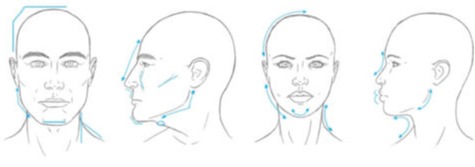

This developing project aims to map the provision and uptake of surgical approaches to facial feminisation across the United Kingdom.